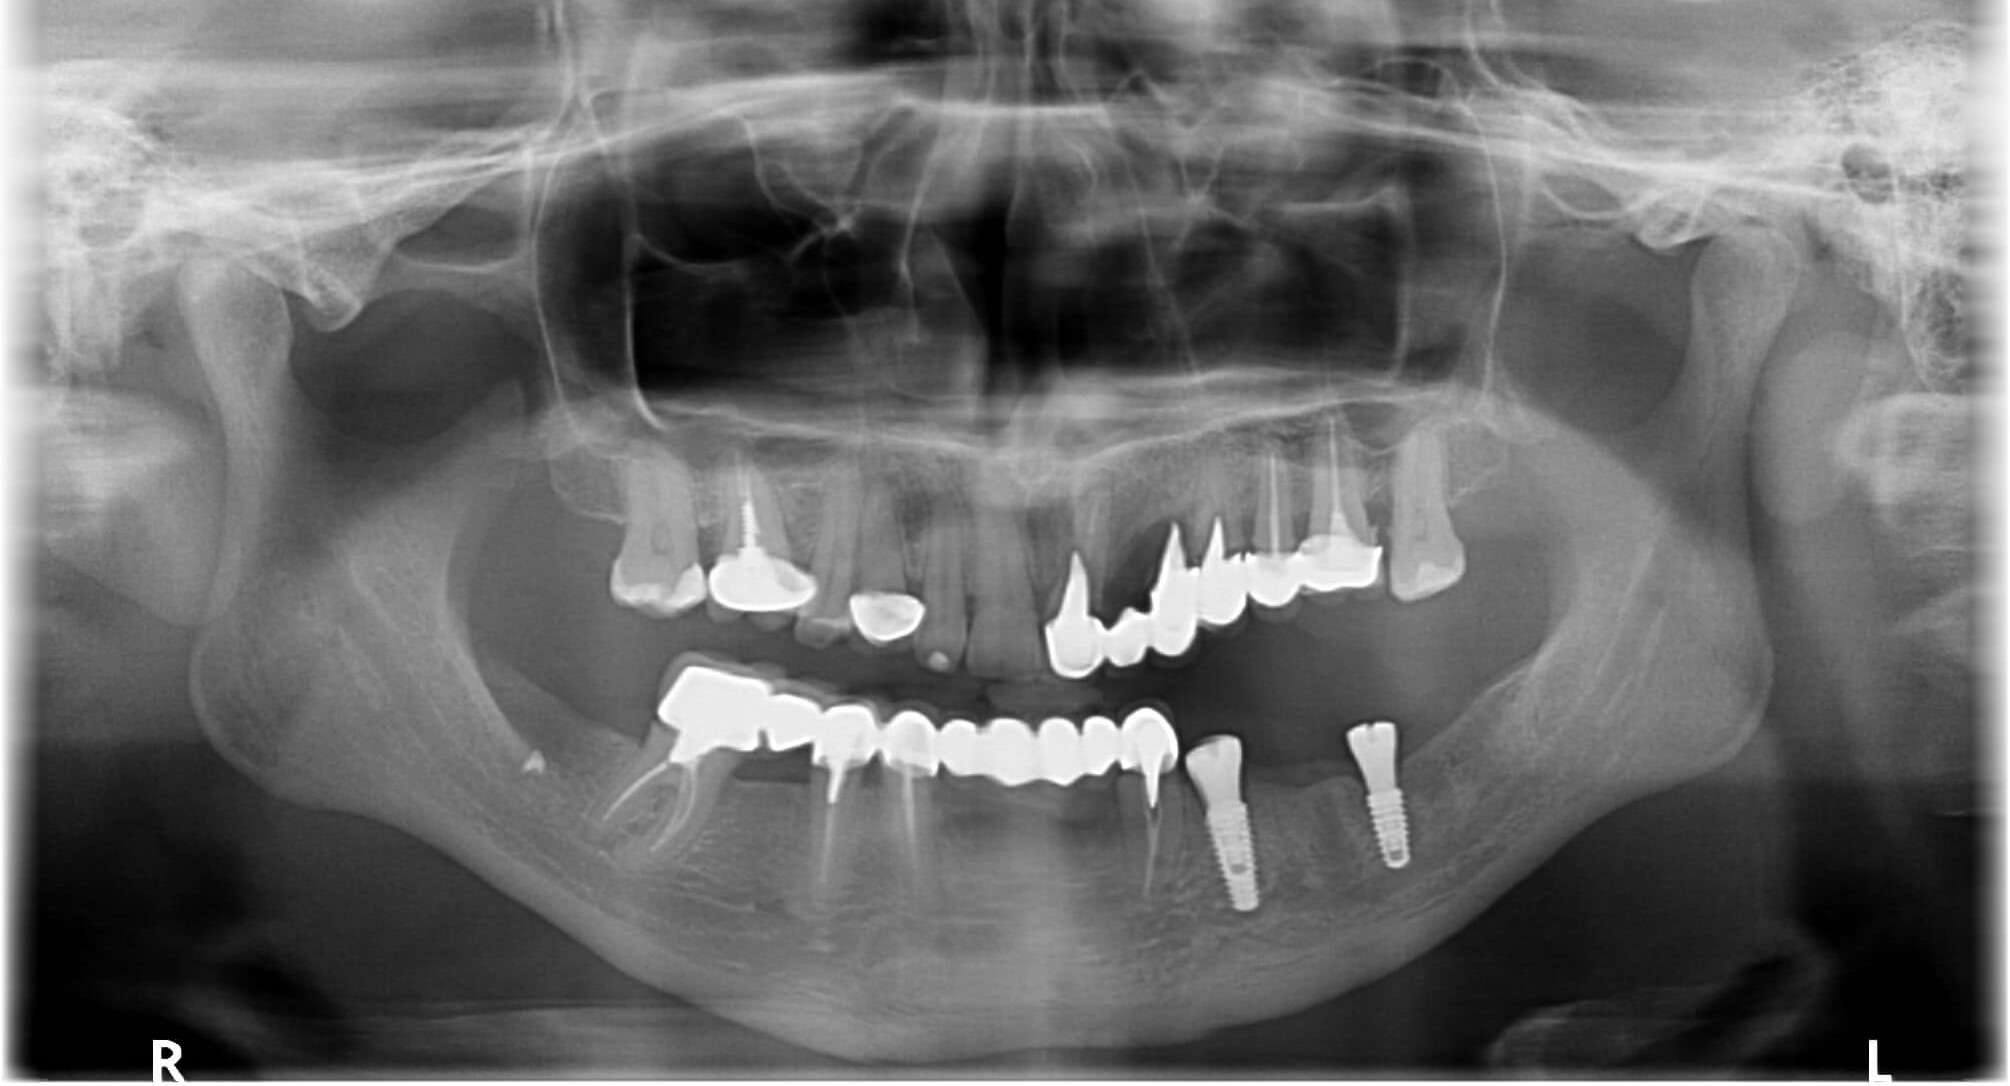

The treatment plan was as follows: first, we removed the old prostheses, treated the remaining teeth, placed implants in the area of missing teeth in the lower left jaw, and provided temporary crowns during the healing period of the implants.

After three months, we restored all the teeth in the lower jaw with zirconia bridges supported by both teeth and implants. The upper teeth were restored with zirconia prostheses, metal-free crowns, and veneers, resulting in an even, symmetrical smile with a brighter and more attractive shade.